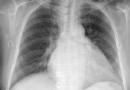

風濕性心髒病是怎麼回事

概 述 相信很多朋友對於風濕性心髒病都並不是十分的了解,那麼風濕性心髒病,主要是因為風濕熱的活動導